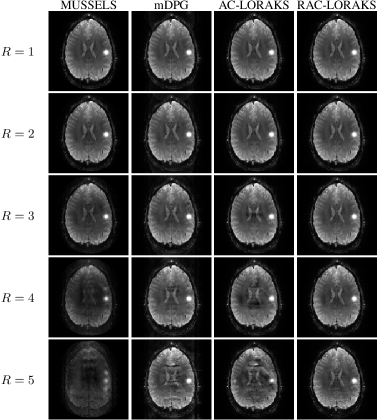

Figure 3 shows reconstruction results from the first set of multi-channel simulations (with similar contrast between ACS and EPI data, but with a hyperintensity added to the EPI data). Quantitative NRMSE values are reported in Table 1 with corresponding ESPs shown in Fig. 4. Qualitatively, the results from Fig. 3 have similar characteristics to the results observed with in vivo data. Notably, RAC-LORAKS is able to consistently reconstruct a high-quality image that bears close resemblance to the gold standard image, while methods like mDPG and AC-LORAKS have artifacts due to the small mismatches between the ACS and EPI data. The visual assessment of reconstruction quality matches well with the quantitative NRMSE assessment shown in Table 1. AC-LORAKS and RAC-LORAKS have a similar performance at and , with RAC-LORAKS having the best performance at high acceleration factors.

Figure 3: Reconstruction results for the first set of multi-channel simulations (with similar contrast between ACS and EPI data, but with a hyperintensity added to the EPI data) with different parallel imaging acceleration factors.

Table 1: NRMSEs for the multi-channel simulation results shown in Fig. 3. For each acceleration factor, the smallest values are highlighted in bold.

| MUSSELS | mDPG | AC-LORAKS | RAC-LORAKS | |

|---|---|---|---|---|

| 0.059 | 0.024 | 0.016 | 0.020 | |

| 0.104 | 0.045 | 0.035 | 0.042 | |

| 0.271 | 0.083 | 0.056 | 0.055 | |

| 0.572 | 0.127 | 0.132 | 0.064 | |

| 0.741 | 0.161 | 0.269 | 0.085 |